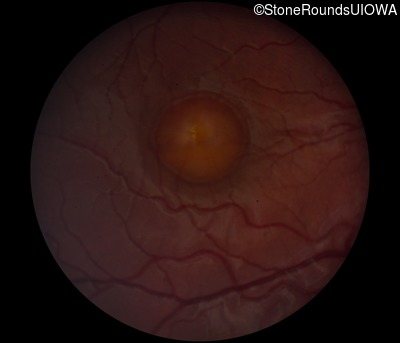

Fundus Photography - Right - 20/40 -1 sc

Exemplar